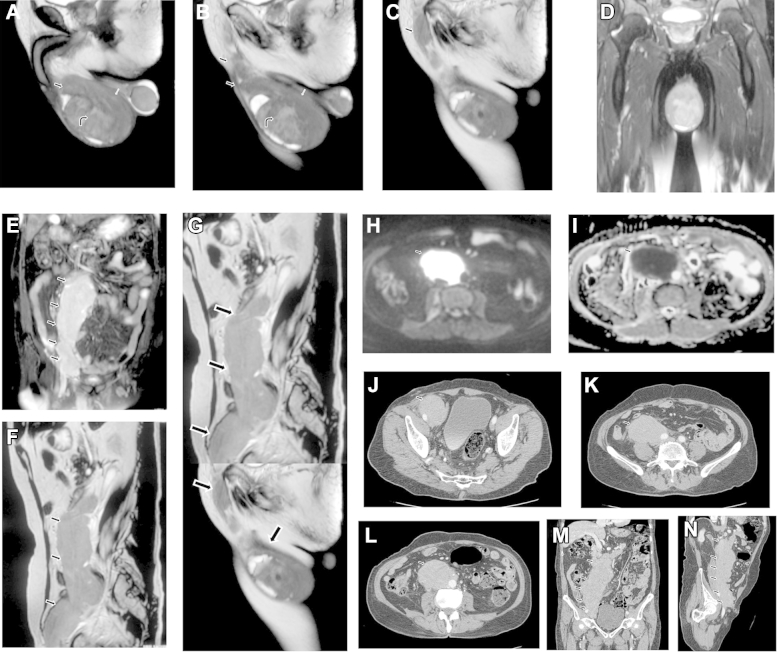

Fig. 1.

An 85-year-old man: (A) Sagittal T2-weighted images of the scrotum - a large heterogeneous T2 isointense-to-hypointense mass lesion seen in the scrotum arising from the right testis and completely replacing it (curved black arrow); (B) the mass was extending along the right epididymis (white arrow) and right spermatic cord (black arrow); and (C) continuous extension of the mass along up to inguinal ring (black arrow). (D) Coronal STIR image of the scrotum of an 85-year-old man: a large heterogeneous STIR hyperintense mass lesion seen in the scrotum arising from the right testis and completely replacing it (black arrow). Magnetic resonance images of the scrotum of the 85-year-old man: (E) coronal STIR image of abdomen: large STIR hyperintense mass lesion is seen extending obliquely from the right inguinal region to the right para-aortic region (black arrow); (F) sagittal T2-weighted image of the abdomen: large T2 isointense-to-hypointense mass lesion is seen extending obliquely from the right inguinal region to the right para-aortic region (black arrow); (G) sagittal T2-weighted pasted image shows continuous extension of the mass lesion from the right testis and epididymis, along the right spermatic cord to the abdomen (black arrow); (H) axial diffusion-weighted image shows increased signals from the mass suggestive of strong diffusion restriction (black arrow); (I) corresponding axial ADC map shows hypointensity within the mass suggestive of strong diffusion restriction (black arrow). Contrast-enhanced CT of the abdomen of the 85-year-old man: (J) axial postcontrast CT image, at the level of external iliac vessels, shows large well-defined homogeneous mass lesion along the right external iliac vessels (black arrow); (K) axial postcontrast CT image, at the level of internal iliac vessels, shows large well-defined homogeneous mass lesion encasing the right gonadal vessels and partly encasing the right external iliac artery (black arrow); (L) axial postcontrast CT image, at the lower para-aortic level, shows large well-defined homogeneous mass lesion along the right gonadal vessels (black arrow); (M) coronal postcontrast CT image shows continuous extension of the homogeneous mass lesion from the right external iliac vessels to the para-aortic region (black arrow); and (N) oblique sagittal postcontrast CT image shows continuous extension of the homogeneous mass lesion from the right inguinal region to the para-aortic region (black arrow).

The patient underwent right inguinal orchiectomy. The histopathology examination revealed diffuse large B cell lymphoma of testis. Further staging workup revealed no other deposits or lymphadenopathy. Contrast computed tomography (CT) abdomen study (part of staging workup) also confirmed homogeneous mildly enhancing soft tissue attenuation mass extending along right gonadal vein with no significant retroperitoneal or mesenteric lymphadenopathy (Figure 1 J to N). Final diagnosis was diffuse large B cell non-Hodgkin lymphoma stage IIAE. The patient was offered chemotherapy and radiotherapy.